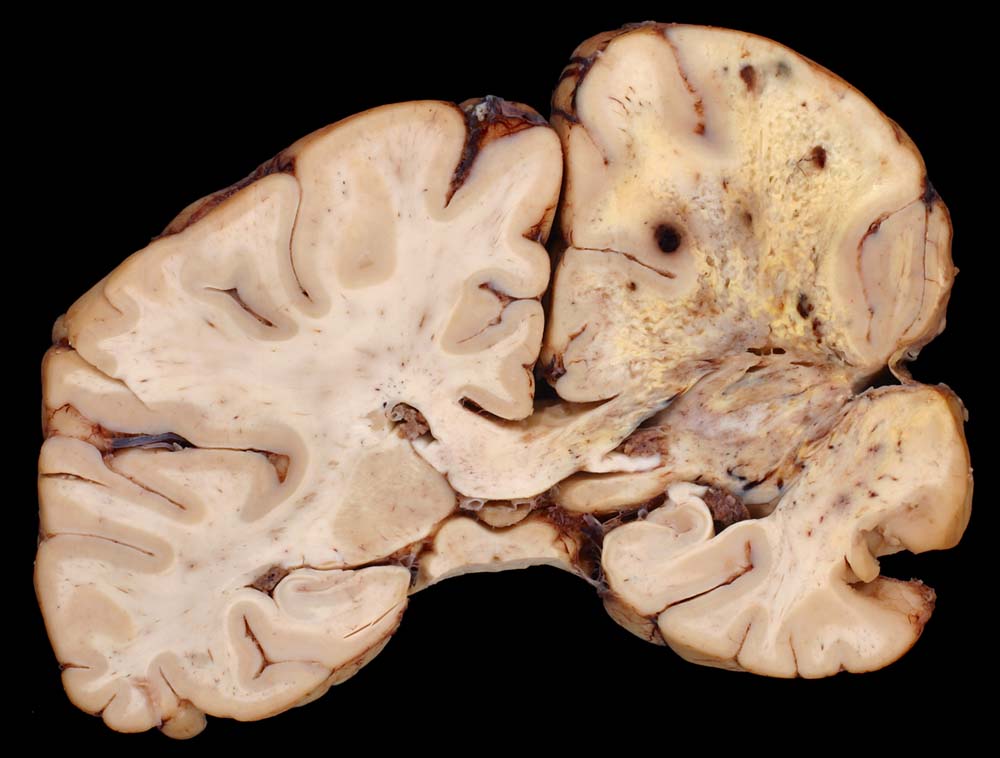

PathoPic ID 8672 - Glioblastoma multiforme (WHO Grad IV)

Glioblastoma multiforme (WHO Grad IV)

Sehr unscharf begrenzter Tumor mit bunter Schnittfläche und ausgedehnten Nekrosen.

Glioblastoma multiforme. Resektionen. Radio- und Chemotherapie, Thalidomid-Therapie.